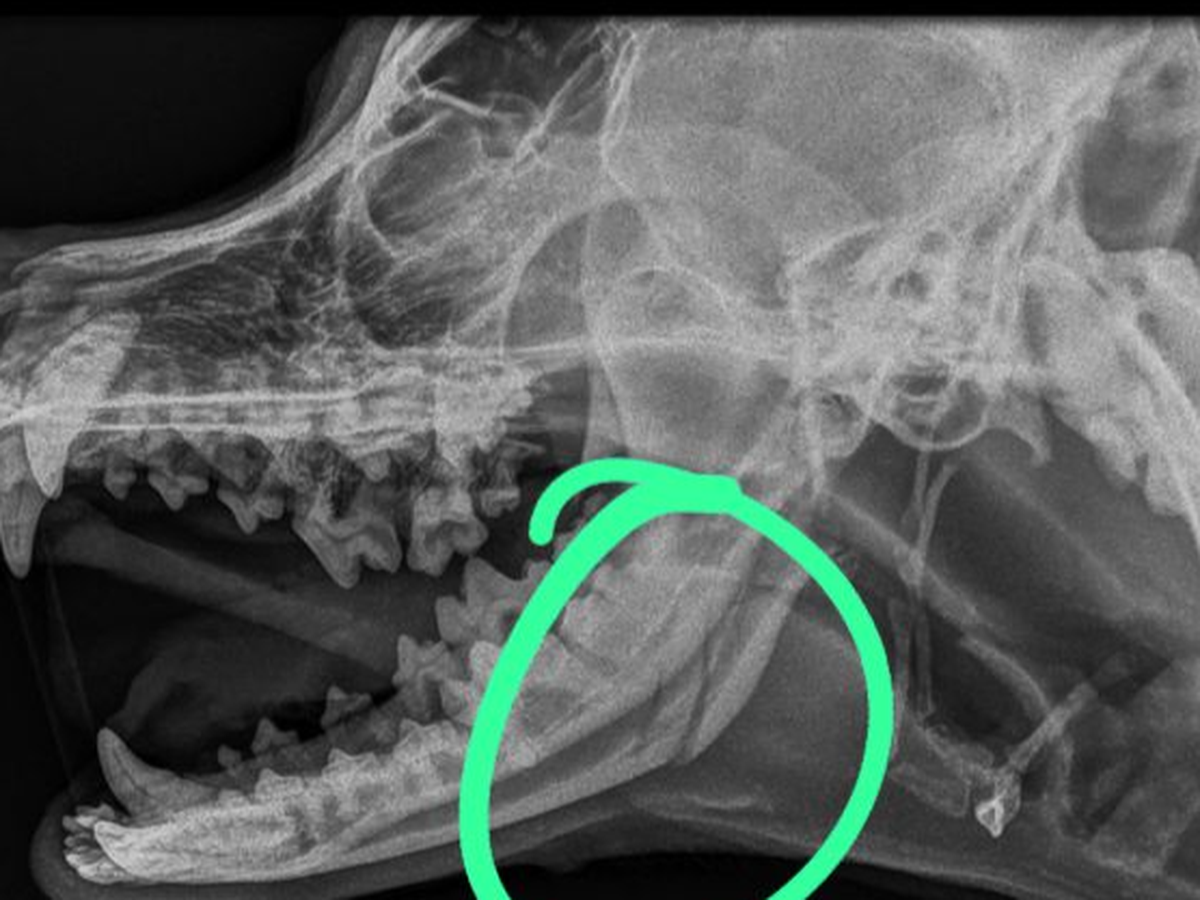

I’m writing with a broken heart and a desperate plea for help. Two days ago, my beloved dogs Coco and Burrito were brutally attacked by several other dogs, leaving them with severe injuries. They have multiple bite wounds and Coco has suffered a broken jaw, which requires immediate surgery to prevent infection and further complications. Without treatment, he could face lifelong issues with eating, drinking, and his overall health. I am deeply worried, but the surgery required to save him is beyond my financial means.

Emergency vet visit for Coco, cranial X-ray, consult with orthopaedic surgeon, surgery, antibiotics, pain management, then whatever ongoing. Care he will need for his recovery